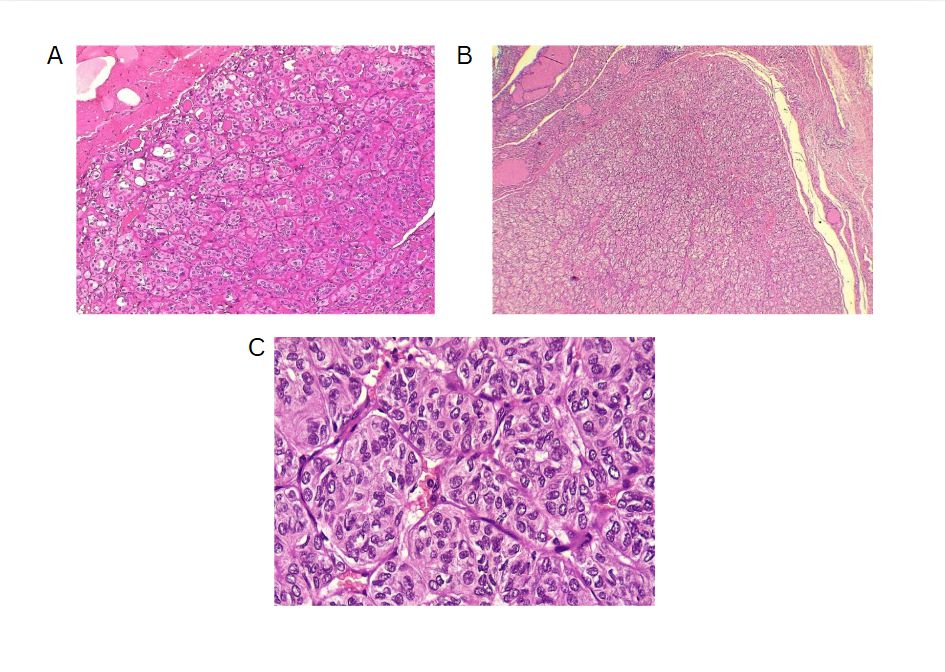

The left thyroid lobe was involved in five cases (45.5%), the right lobe in four cases (36.4%), and the isthmus in two cases (18.1%). The primary surgical approach was total thyroidectomy in seven cases (63.6%), including one patient who underwent concurrent neck dissection (Table 2). Tumor size ranged from 0.5 to 5.5 cm, with a mean size of 2.6 cm (Table 3). All the diagnoses were made post-operatively through histopathological examination (Figure 1).

On gross examination, HTT typically presents as a solid, well-circumscribed mass, or less commonly, as an encapsulated tumor, with colors ranging from yellow to tan, opposite to PTC, which is usually white and does not have a capsule. HTT generally lacks invasion into the capsule, vasculature, or thyroid parenchyma [5,7]. However, Gowrishankar reported a case in which invasion and malignant behavior were observed in HTT [13].